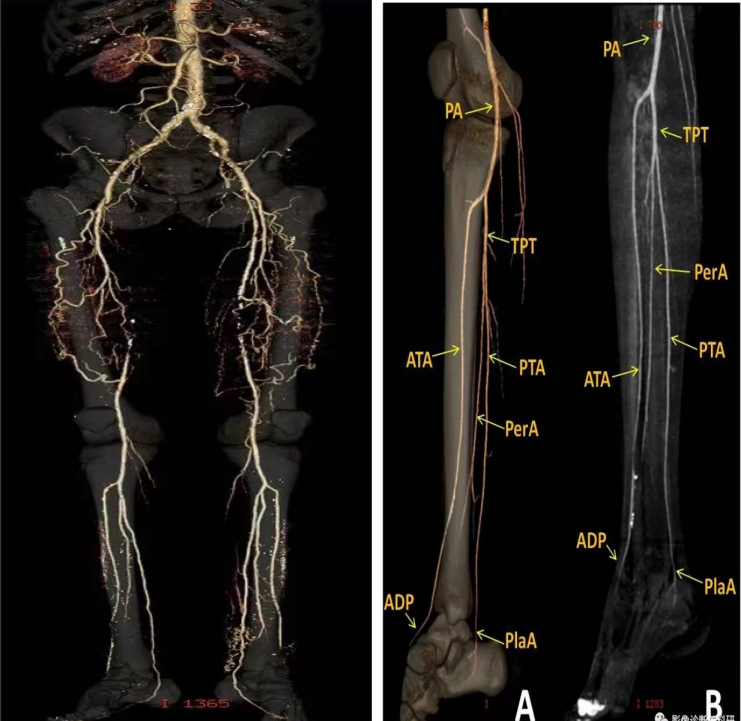

【新技術(shù) 新業(yè)務(wù)】雙下肢動脈CTA和靜脈CTV檢查

近日,我院放射科與外科共同協(xié)作,成功實施了雙下肢動靜脈CTA及CTV檢查技術(shù)。該技術(shù)的成功開展標(biāo)志著我院在放射診斷技術(shù)領(lǐng)域的又一次突破,不僅提升了放射科CT檢查水平,更填補了我院在該項檢查技術(shù)上的空白。 01 什么是下肢動脈CTA、靜脈CTV檢查? 雙下肢靜脈CTV、動脈CTA是用含碘對比劑和CT成像設(shè)備進行動、靜脈疾病評估及診斷的成像技術(shù)。可通過多方位多層面重建技術(shù),明確下肢動、靜脈血管的狹窄、擴張程度以及斑塊情況,并定位準(zhǔn)確、直觀。雙下肢動脈CTA及雙下肢靜脈CTV作為一種可靠的無創(chuàng)性檢查方法,可以部分取代DSA等有創(chuàng)技術(shù)對下肢動、靜脈的診斷。 02 下肢動脈CTA、靜脈CTV檢查的優(yōu)勢? 目前,臨床廣泛應(yīng)用于靜脈血管檢查的影像學(xué)方法是彩色多普勒超聲,它具有無創(chuàng)無輻射、不需要對比劑、檢查方便快捷和費用低廉經(jīng)濟等優(yōu)點,由于靜脈具有較大的變形性,使得該檢查的準(zhǔn)確性欠佳,一些深部血管比如鎖骨下靜脈、頭臂靜脈、上腔靜脈等仍然屬于該檢查的“盲區(qū)”,且其無法提供完整的血管走行影像,因此多普勒超聲僅適用于初步篩查。 數(shù)字減影血管造影(digital subtractionangiography,DSA)由于其空間分辨力高,是目前血管檢查的金標(biāo)準(zhǔn),但其屬于有創(chuàng)檢查,具有一定創(chuàng)傷性,檢查期間患者需要住院、費用高、且操作復(fù)雜。 與之相比,動脈CTA、靜脈CTV檢查具有較明顯的優(yōu)勢:血管圖像分辨率高,堪與DSA相媲美;無創(chuàng),減輕患者痛苦;觀察全面,一次靜脈注射就可以顯示所有需要的血管圖像,可以在術(shù)前對血管的變異情況、走行、內(nèi)徑大小、分支等進行準(zhǔn)確測定,為臨床的進一步診治提供有效的信息。 03 下肢動脈CTA、靜脈CTV檢查適應(yīng)癥 下肢動脈CTA適應(yīng)癥: 1、動脈硬化閉塞; 2、外傷后下肢動脈損傷; 3、急性血栓; 4、真性動脈瘤、假性動脈瘤、夾層動脈瘤及動靜脈瘺; 5、動脈支架術(shù)后復(fù)查及再狹窄的評估等。 下肢靜脈CTV適應(yīng)癥: 1、存在潰瘍或壞疽或跛行癥狀時的缺血程度的評估; 2、大血管疾病評估:變異、破裂、動靜脈畸形、脈管炎; 3、下肢靜脈血栓形成,適用于其他檢查的診斷結(jié)果不清楚的情況; 4、腫瘤引起的血管侵犯或移位; 5、手術(shù)或血管介入的術(shù)前術(shù)后評估。